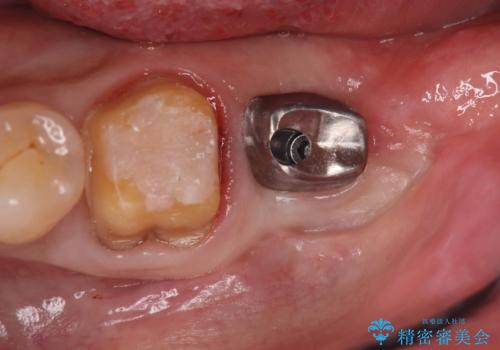

検査の結果、左下7番は歯周ポケットが8mmと深く、レントゲンでも根尖部から骨が溶けている状態が確認されました。エンドペリオ病変と診断し、精密根管治療による保存か、抜歯をしてインプラントで治療するかをご提案したところ、患者様は抜歯・インプラント治療を希望されました。

また、左下6番は銀歯と虫歯を除去した後、見た目や適合性に優れたオールセラミッククラウンで修復を行いました。